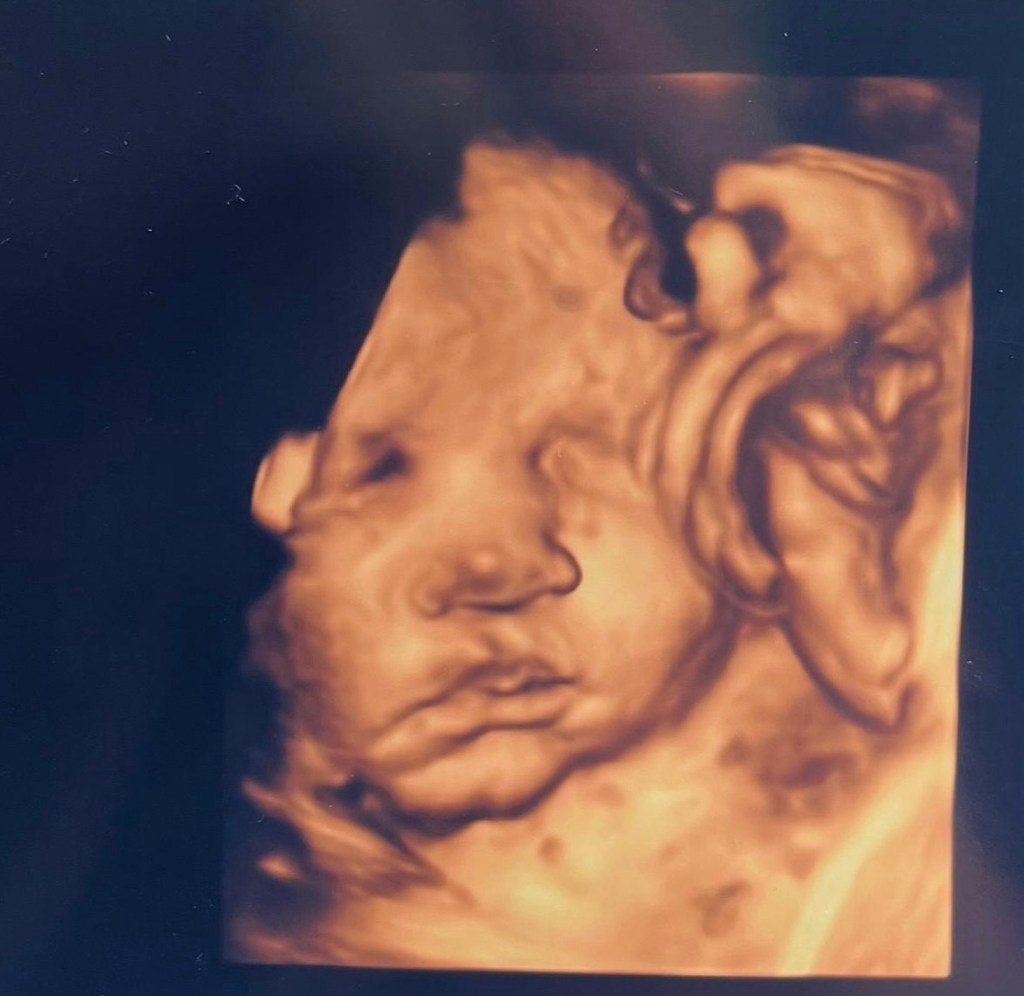

Her zaman kız çocuğu istedim. Ve içimde de hep kız çocuğu vardı hissiyat… 🙂 ama o gün🤣 herkes diyor erkek erkek erkek.. video da göreceksin onlara düşüp ben de erkek dedim😅 ama her zaman kızım olsun en yakın arkadaşım olsun hep istedim. İyi ki meleğim💗